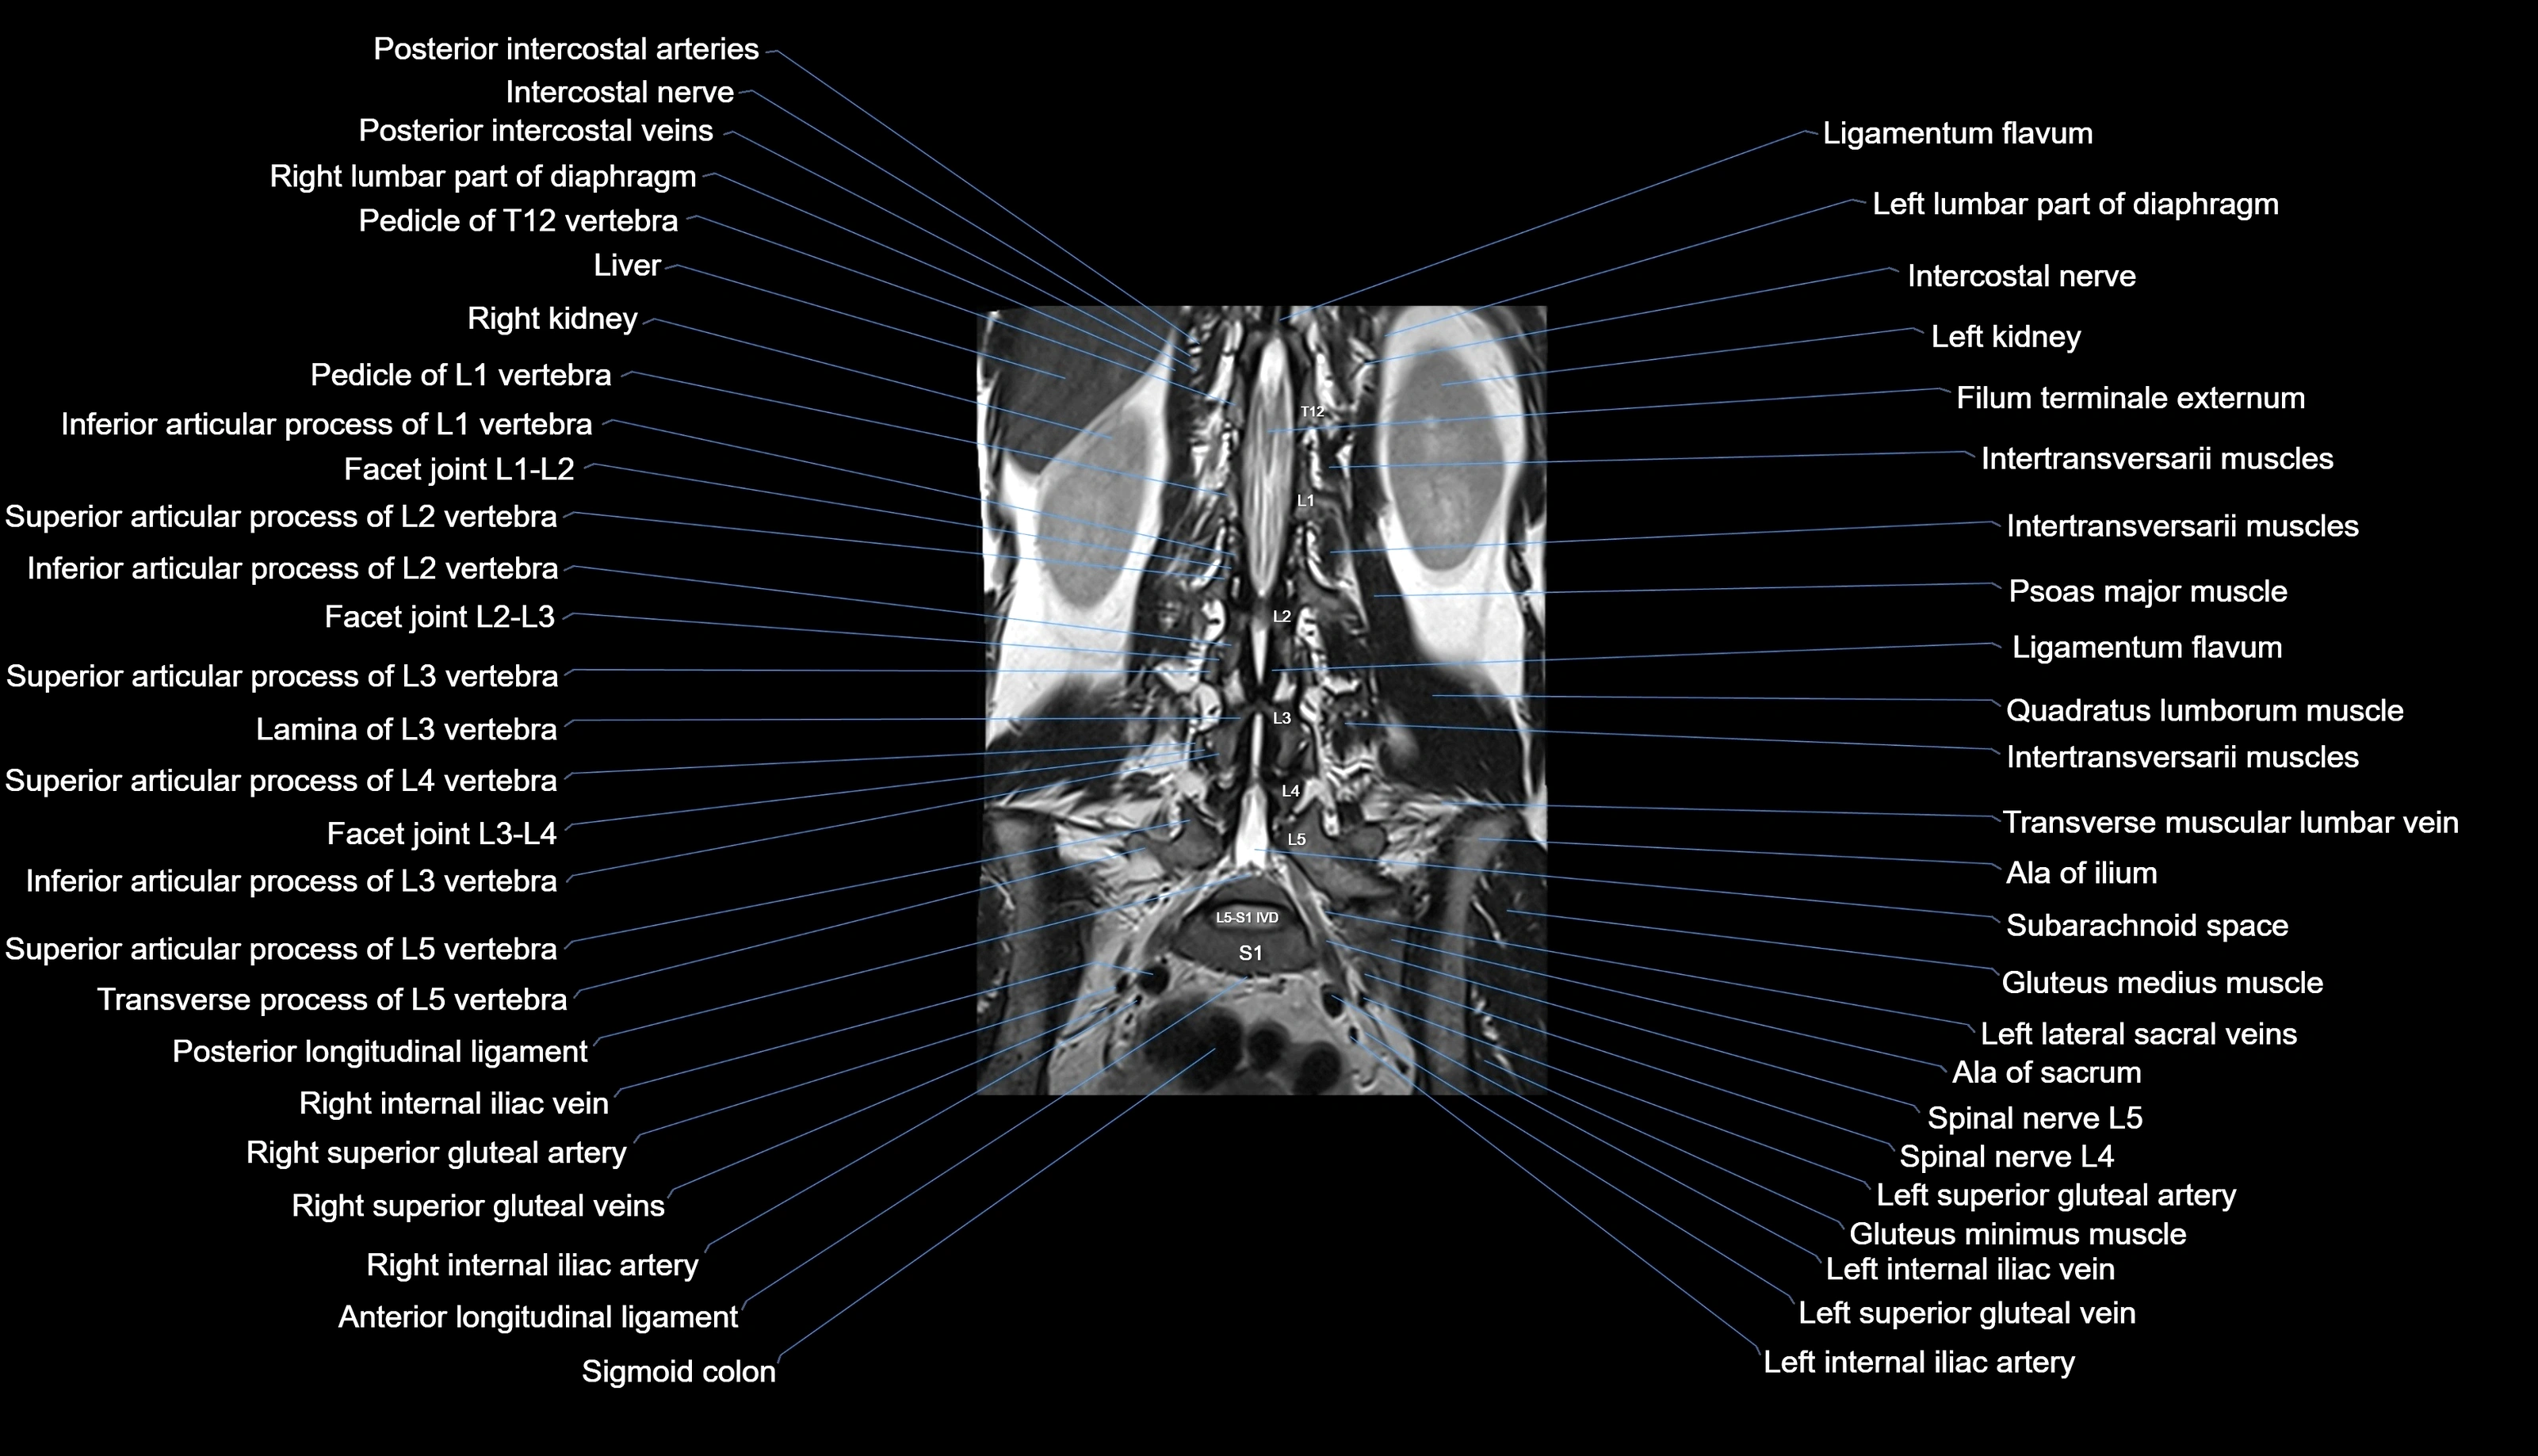

MRI images